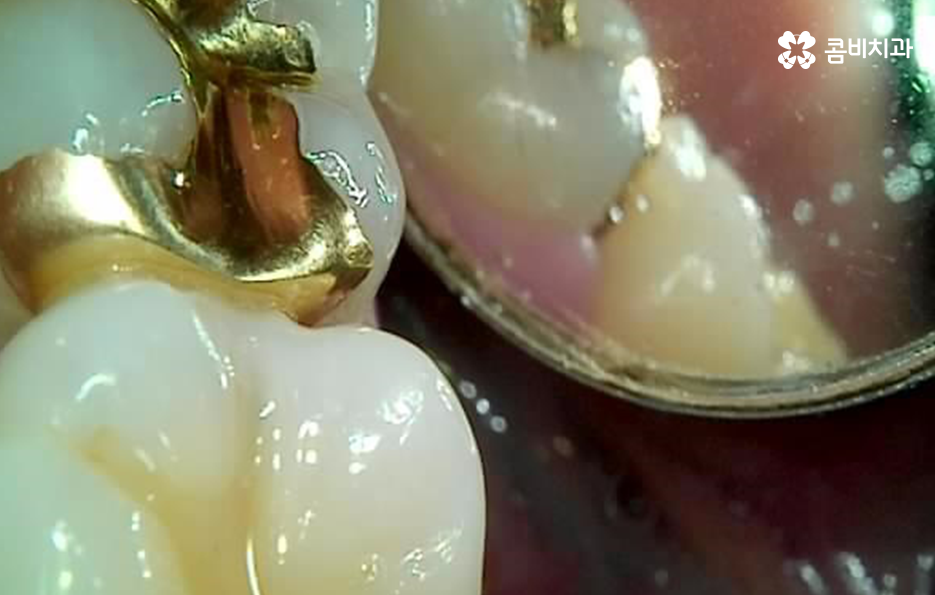

위에 보시는 것처럼 금 인레이의 경우 치아의 삭제를 줄일 수 있는 치료 방법으로 금 인레이 자체가 내구성이 튼튼하고 생체친화적이며 얇게 제작을 해도 어금니 처럼 강한 압력을 받는 치아에도 치료가 가능하기 때문에 치아 보존에 유리한 재료라고 할 수 있는데요